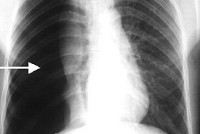

Для правильной оценки характера повреждений обязательна рентгенография грудной клетки в двух проекциях. Рентгенологическое исследование позволяет выявить смещение средостения и коллапс легкого (при гемо- и пневмотораксе), пятнистые очаговые тени и ателектазы (при ушибах легкого), пневматоцеле (при разрыве мелких бронхов), эмфизема средостения (при разрыве крупных бронхов) и другие характерные признаки различных повреждений легких. Если позволяют состояние пациента и технические возможности, желательно уточнение рентгеновских данных с помощью компьютерной томографии.